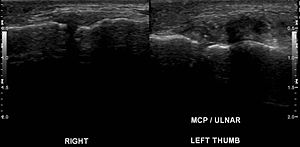

좌측 정상 인대 / 우측 파열된 손가락 인대@위키피디아

위의 초음파 이미지를 보면우측의 인대가파열되어퉁퉁 부어있습니다.오랫동안 잘 낫지 않는 경우위 그림처럼인대가 파열되면서뼈 조각이 떨어져나가거나뼈에 금이 갔던 경우가 많습니다.문제는골절 초기에X-ray상 잘 안보인다는 겁니다.1주일 정도 지나면서출혈도 생기고골절된 부위가 더 벌어지면뒤늦게 발견되는 경우가 많습니다.골절인지도 모르고열심히 스트레칭해서 벌려놓으면후유증이 오래 가겠죠.